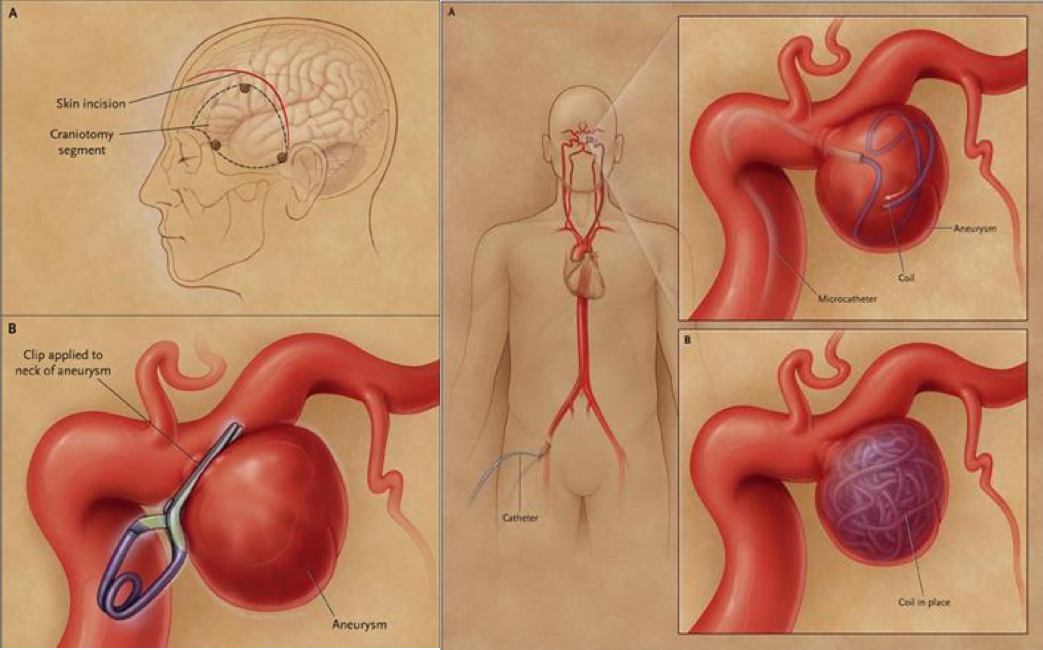

The EM resident adds that if this turns out to be an SAH, Jennifer will go in for a cerebral catheter angiography to find the most likely cause of the bleeding. If it is the berry aneurysm as we suspect, it will either be coiled or clipped to stop the bleeding.

What does “coiled or clipped” mean?

The resident explains that Jennifer will either get the aneurysm cut off with a surgical clip to close off the pouch, or a wire will be inserted by interventional radiologythat will fill up the pouch and eventually clot and scar off. Sometimes a stent is placed in especially wide necked aneurysms to facilitate repair. The latter is preferred all else being equal as it does not require opening the skull.

Medscape – on the left, a surgical clip, on the right, a coiling through interventional radiology.